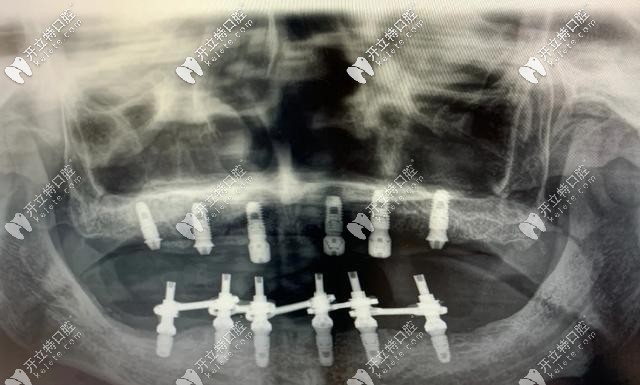

即刻負(fù)重種植牙主要針對全口無牙頜或半口無牙的情況下,每個(gè)半頜4-6顆種植牙就可以恢復(fù)半口的牙齒,術(shù)后2個(gè)小時(shí)即可戴牙進(jìn)食,實(shí)現(xiàn)了當(dāng)天種當(dāng)天用。

即刻負(fù)重種植牙對骨質(zhì)要求比較高,牙槽骨骨量得充足,種植體長度大于10mm,直徑大于3.5mm,一般單顆牙缺失不適合即刻負(fù)重,適用于口內(nèi)多顆或全部牙齒缺失的人群。